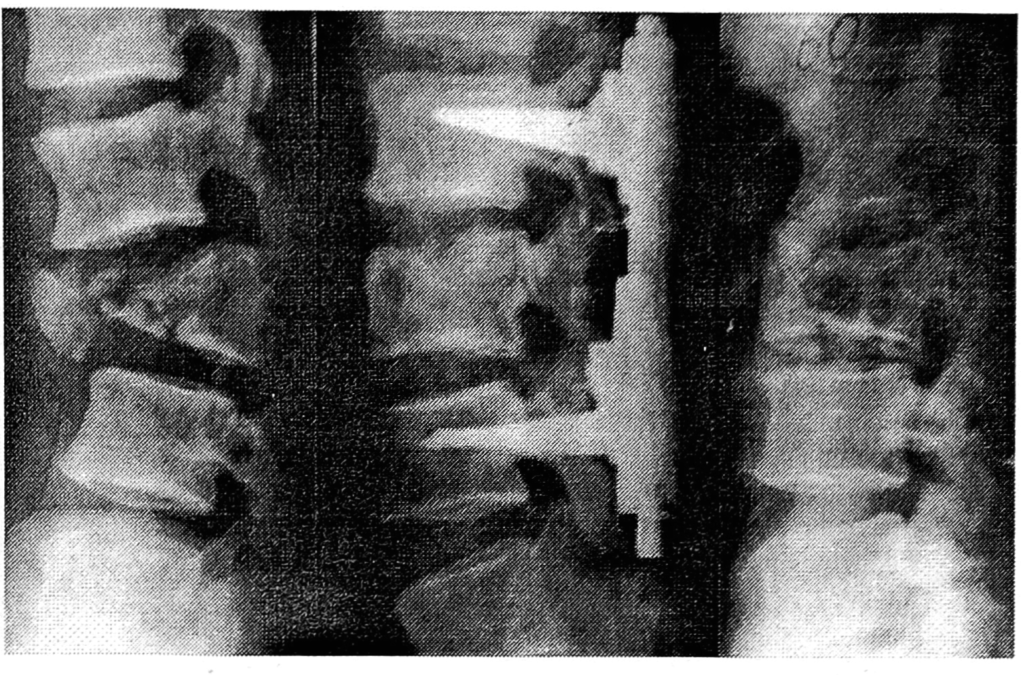

Показаниями к оперативному лечению из заднего доступа являлись рецидивирующие, невправимые свежие и несвежие (до 4 нед) одно- и двусторонние вывихи, как осложненные повреждением спинного мозга, так и без неврологической симптоматики. Мы отдаем предпочтение интерламинарной фиксации. В нашем центре для дорсальной стабилизации шейного отдела используются титановые конструкции с набором монтажного инструмента, разработанные совместно с фирмой «Медбиотех» (рис. 2). С применением этих конструкций и некоторых других фиксаторов оперировано 60 пациентов. Во всех случаях достигнута интраоперационная коррекция и прочная фиксация позвоночных сегментов, что позволило активизировать пациентов в раннем послеоперационном периоде с минимальным использованием внешней иммобилизации легкими ортезами. Применение диамагнитных титановых фиксаторов обеспечило возможность проведения в послеоперационном периоде компьютерной и магнито-резонансной томографии для оценки состояния позвоночного канала и спинного мозга.

Рис. 2. Рентгенограммы позвоночника больного с двусторонним сцепившимся вывихом С5 позвонка до операции и после интерламинарной фиксации конструкциями фирмы «Медбиотех».